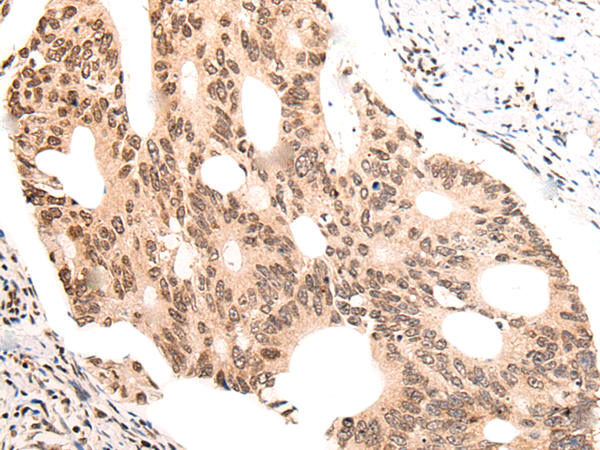

IHC positive control: |

Human colorectal cancer and human liver cancer |

IHC Recommend dilution: |

40-200 |